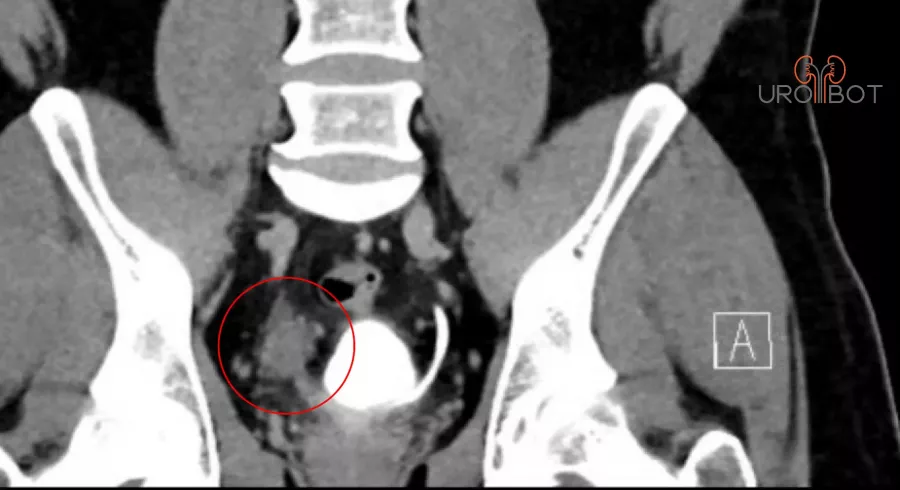

Harnleiterkarzinom

Bei einer Harnleiterteilresektion wird ein Teil des Harnleiters entfernt, weil er zum Beispiel durch einen Tumor befallen ist oder wegen einer Verengung nicht mehr durchgängig ist.

In Abhängigkeit der Lage im Harnleiter kann die Blase "verlängert" und hochgezogen werden oder der Harnleiter wird durch ein Stück Darm ersetzt.